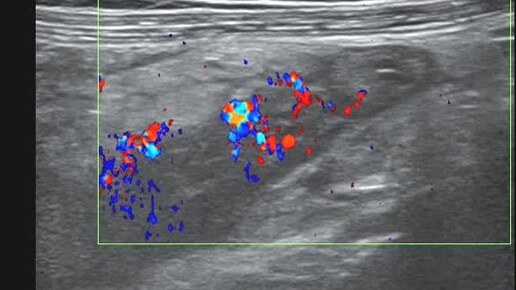

Ультразвуковые находки от врача УЗД Зорина Я.П.